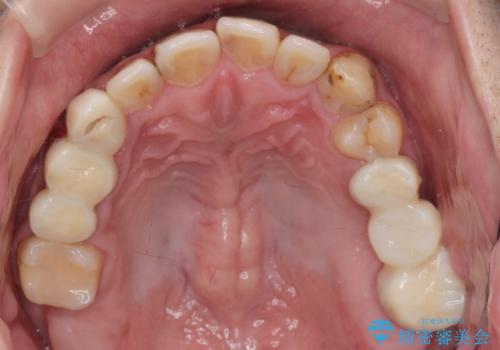

- 口の中をマスク生活の間に全て治したい、見た目を良くしたいとの事で来院。

まず徹底的に虫歯を取り除き、保存が出来ない部位は抜歯(親知らずを含む)を行い、根管治療が必要な部位は精密根管治療を行いました。

その後、インプラント治療、セラミック治療を行いました。

一度治療するはを全て仮歯に変えて、歯茎を整えてからセラミックを装着しました。

また、虫歯が歯肉の中まである場合はAPF(歯肉弁根尖側移動術)も行なっています。